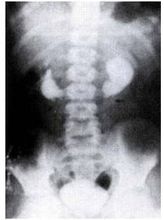

馬蹄腎的IVU所見排泄性尿路造影可見兩側腎盂腎盞位置低,而且兩腎下極靠近脊柱,故腎下極的延長

線與正常腎盂相反,在尾側方向交叉。由於鏇轉不良腎盂腎盞多重疊,甚至腎盞指向內側,腎盂轉到外

側,上段輸尿管向外彎曲。有時輸尿管受血管、纖維帶或峽部壓迫可引起腎積水。仔細觀察,在KUB平片上有時可見軸線健康搜尋不正常的腎及峽部的陰影。